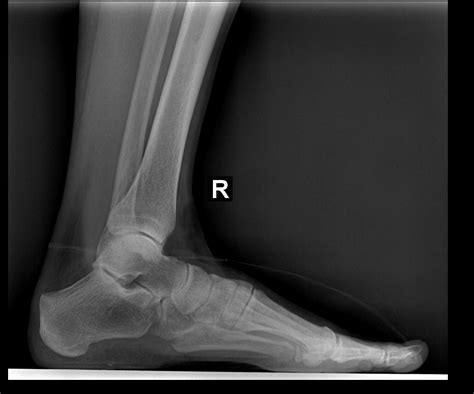

Obtaining a lateral foot X ray is a straightforward process that typically involves the following steps:

• Patient Preparation: The patient is asked to remove any jewelry or metal objects from the foot area to avoid interference with the X-ray image.

• Positioning: The patient stands or sits with the foot placed on a platform. The foot is positioned at a 90-degree angle to the X-ray beam to ensure a true lateral view.

• Imaging: The radiographer takes the X-ray, and the image is captured on a digital detector or film.

• Review: The radiologist reviews the image to ensure it is of diagnostic quality and interprets the findings.